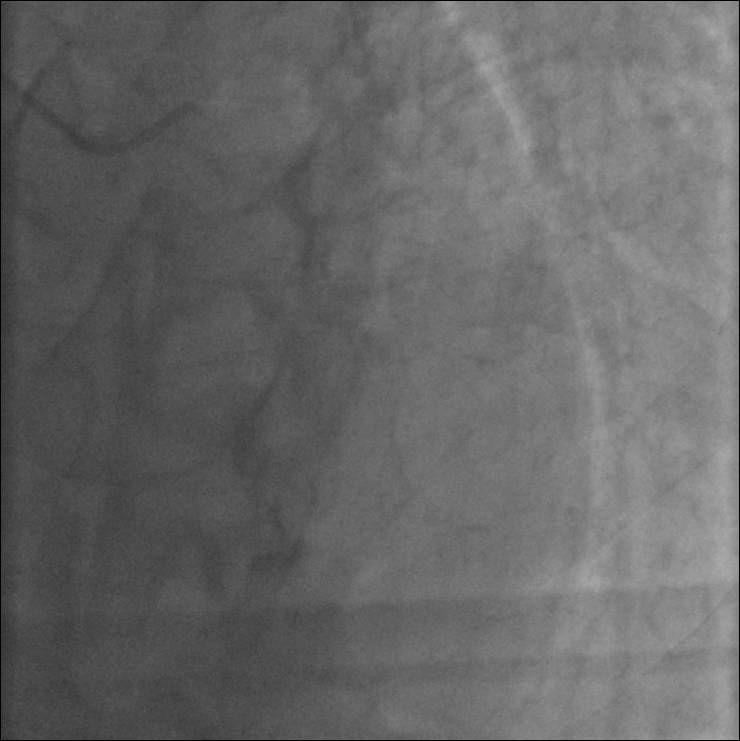

冠脉造影结果

2016-11-26(13点30分)